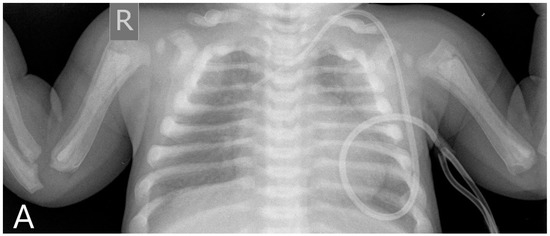

A six-month-old male patient diagnosed with ARO was admitted to our transplantation unit. The patient’s clinical presentation was characteristic of the disease: deformed sclerotic skull, multiple fractures, optic nerve atrophy with progressive visual impairment, and thrombocytopaenia with hepatosplenomegaly as the sign of bone marrow involvement. The auditory system is often affected in ARO, but the patient showed no sign for otologic involvement of the disease at this time. Diagnostic radiography of the chest and cranial MRI can be seen in Figure 1.

Figure 1.

Pre-transplantation radiography (A) shows increased bone density, rachitic malformation in ribs, and endobone appearance in vertebrae and humeri. Sagittal T1-weighted MR image (B) demonstrates the sclerosis of the calvaria. Axial T2-weighted MR image (C) shows optic canal stenosis and optic nerve atrophy.